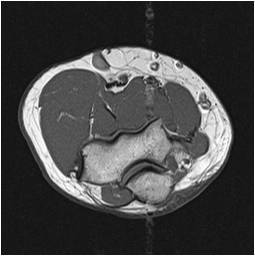

Radiograph #2

Distal Arm and Elbow

Identify: Radial nerve, brachial artery, biceps tendon, basilic vein, cephalic vein, brachialis, Brachioradialis, olecranon process, oleranon fossa, ulnar nerve, median cubital vein, ulnar groove, pronator teres, flexor carpi ulnaris.